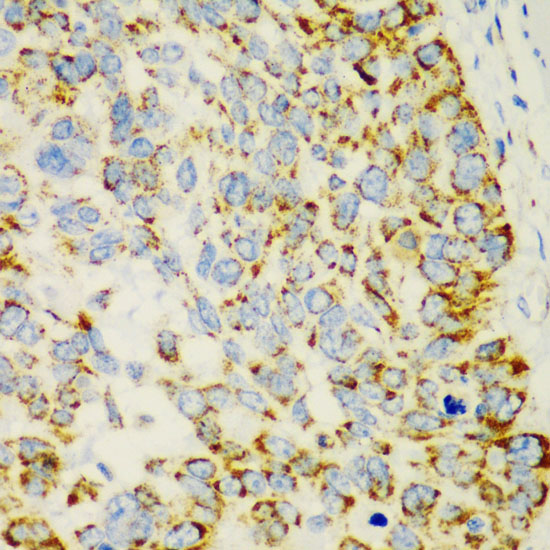

Contributes to the response to IL-13 and inflammation in response to IL-13. Stimulates chemokine production by pulmonary epithelial cells.

Detected in lung epithelial cells from asthma patients (at protein level). Highly expressed in stomach. Detected at lower levels in lung.

[Isoform 1]: Secreted. Secretion depends on EGFR activity.; [Isoform 2]: Cytoplasm.; [Isoform 3]: Cytoplasm.